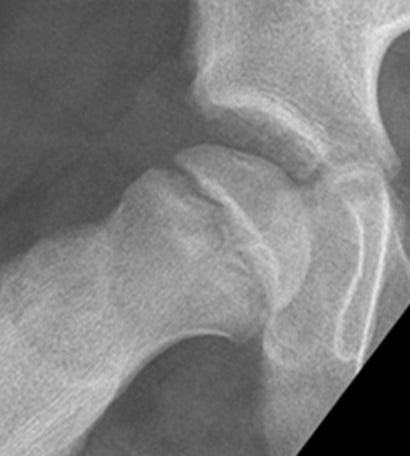

Slipped Capital Femoral Epiphysis (SCFE) or femoral epiphysiolysis is an idiopathic Salter-Harris type I fracture of the proximal femoral epiphysis. It occurs more commonly in boys and in obese children. The typical age at presentation is between 12-15 years. SCFE may occur bilaterally in up to one third of cases. As the epiphysis slips posteriorly, and to a lesser extent medially it is best appreciated on the frog-leg lateral view (Fig.5). SCFE is treated with surgical fixation to prevent further slip off. Avascular necrosis of the femoral epiphysis is a potential complication.

Figure 5. Lauenstein view with right (H) sided slipped capital epiphysis.